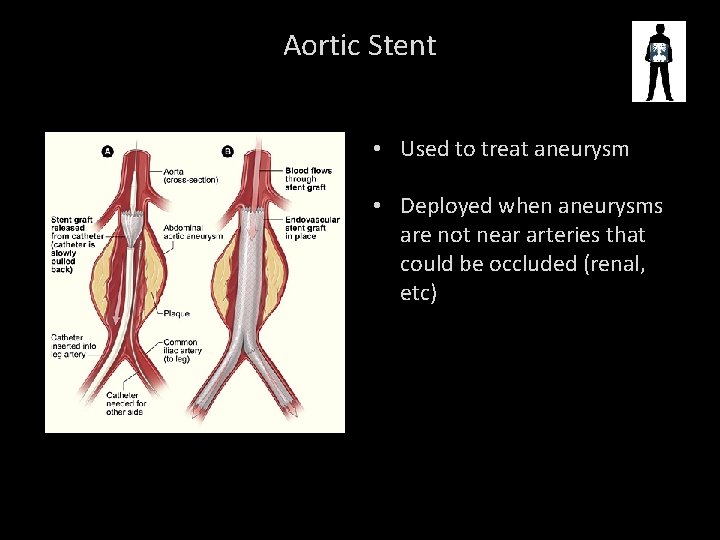

Aortic Stent • Used to treat aneurysm • Deployed when aneurysms are not near arteries that could be occluded (renal, etc)